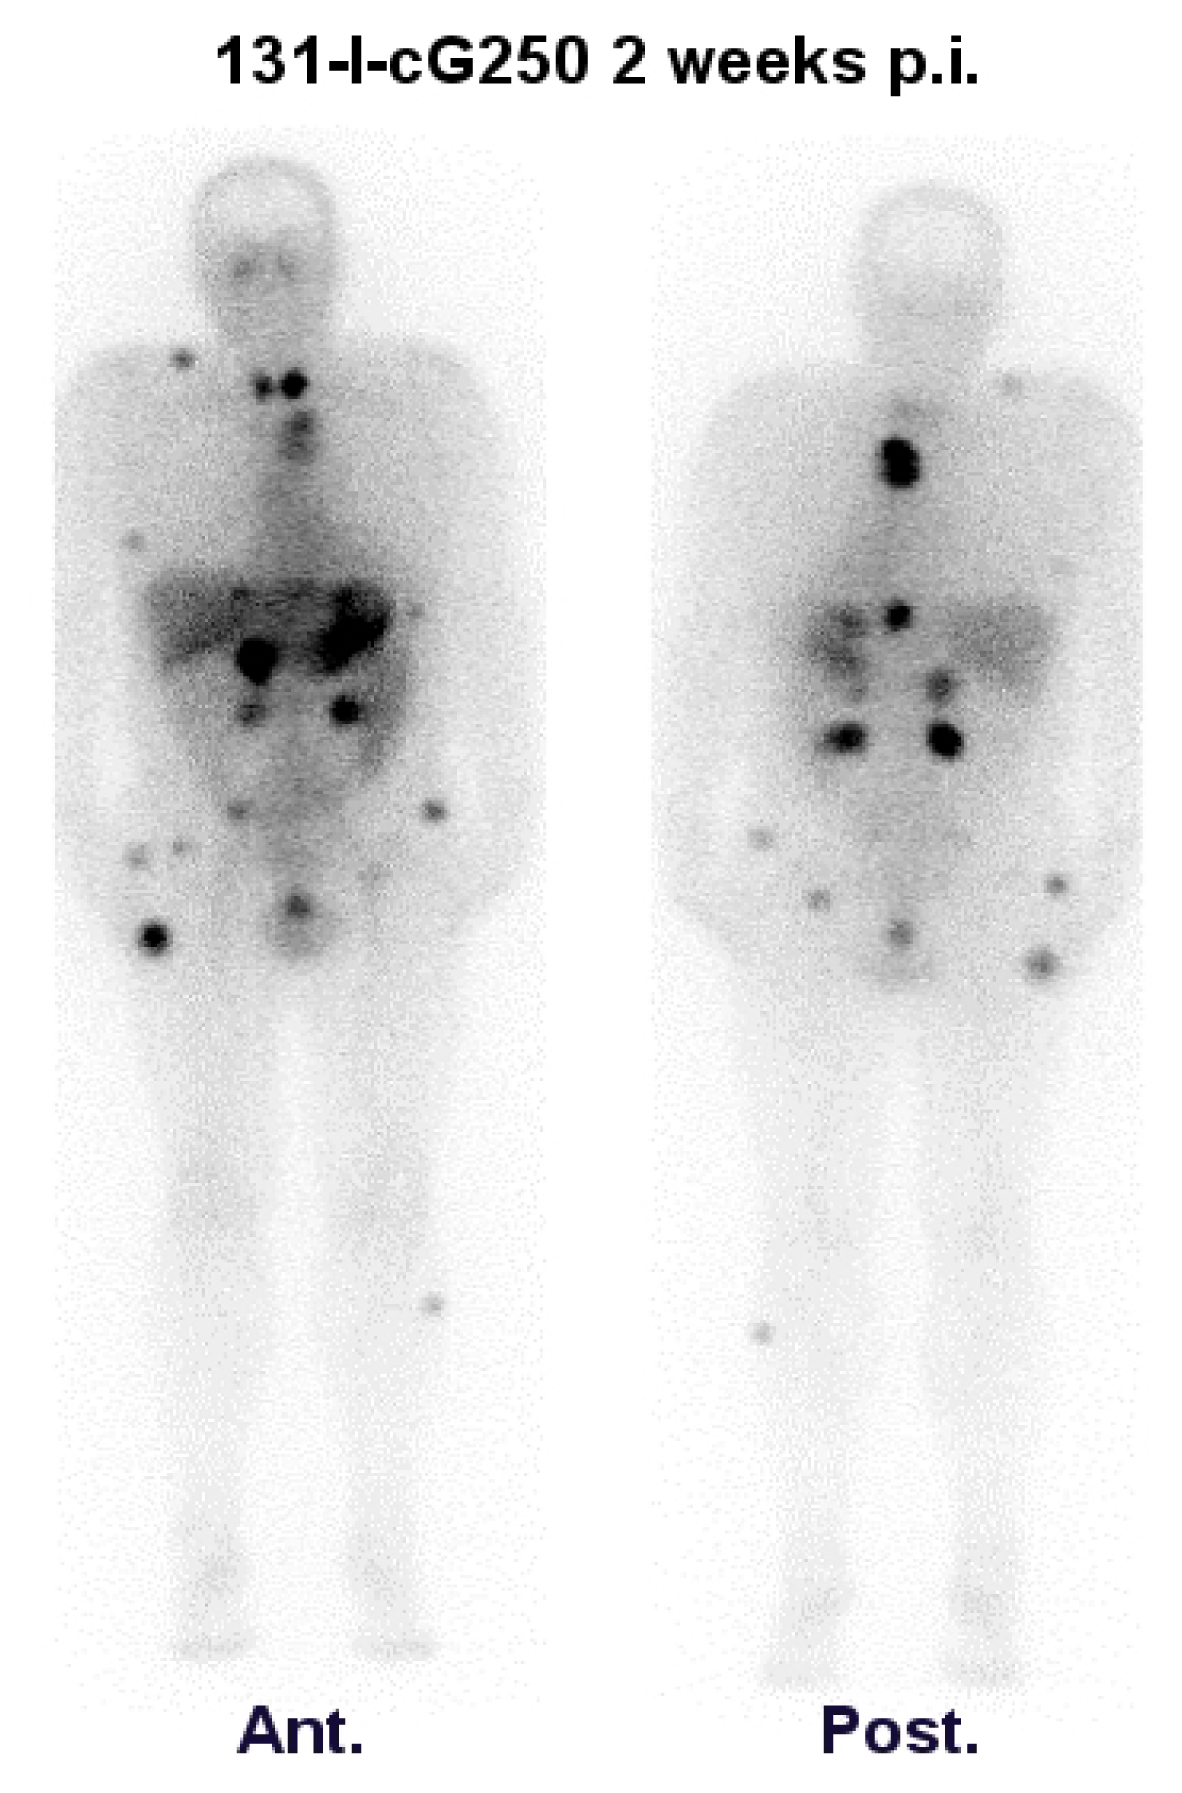

- Brouwers, A.H.; Dorr, U.; Lang, O.; Boerman, O.C.; Oyen, W.J.; Steffens, M.G.; Oosterwijk, E.; Mergenthaler, H.G.; Bihl, H.; Corstens, F.H. 131I-cg250 monoclonal antibody immunoscintigraphy vs. [18F]fdg-pet imaging in patients with metastatic renal cell carcinoma: A comparative study. Nucl. Med. Commun 2002, 23, 229–236. [Google Scholar]

- Brouwers, A.H.; Buijs, W.C.; Oosterwijk, E.; Boerman, O.C.; Mala, C.; de Mulder, P.H.; Corstens, F.H.; Mulders, P.F.; Oyen, W.J. Targeting of metastatic renal cell carcinoma with the chimeric monoclonal antibody g250 labeled with 131I or 111In: An intrapatient comparison. Clin. Cancer Res 2003, 9, 3953S–3960S. [Google Scholar]

| Brouwers et al. [32] | 2002 | 131I-cG250 vs. 18F-FDG | 20 | M + RCC | 131I-cG250: 34/112 lesions 18F-FDG: 77/112 lesions | Comparative intrapatient study |

| Brouwers et al. [33] | 2003 | 131I-cG250 & 111In-cG250 | 5 | M + RCC | 111In-cG250: 47 lesions 131I-cG250: 30 lesions | Comparative intrapatient study |